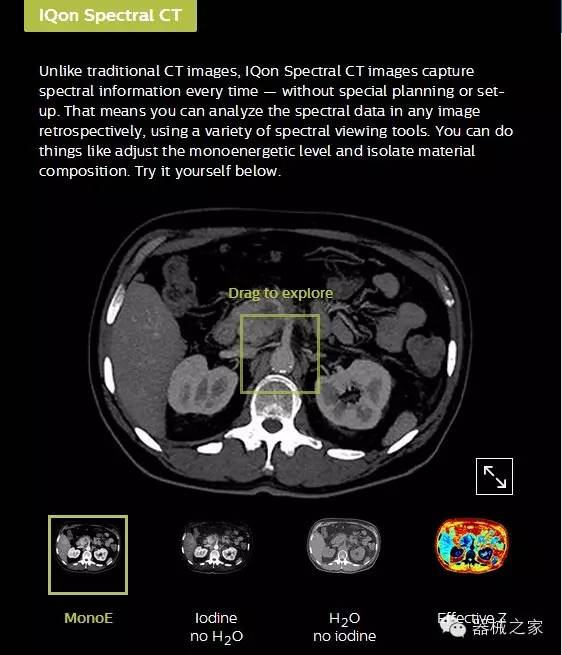

IQon光譜CT能夠按照需求提供光譜量化和工具,并能通過簡單工作流程、在低劑量下對(duì)結(jié)構(gòu)進(jìn)行定性分析

IQon光譜CT -- 是業(yè)界首臺(tái)以探測(cè)器為成像基礎(chǔ)的光譜CT,它可以在單次常規(guī)掃描下獲得傳統(tǒng)解剖影像及光譜功能影像。不僅可以提供精準(zhǔn)的診斷信息,還可簡化工作流程、在低劑量下完成定量與定性分析。